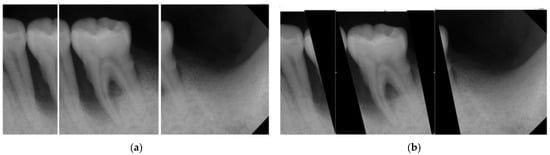

| Original Images | Gaussian High-Pass Filter | Gaussian High-Pass Filter + Mask | |

|---|---|---|---|

| Validation Accuracy | 84.16% | 87.21% | 94.97% |

| Validation Loss | 0.7634 | 0.4578 | 0.1822 |

| Image | ![]() | ![]() | ![]() |